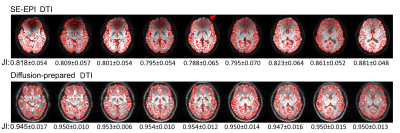

Figure 3. Geometric distortions in axial SE-EPI (top row) and diffusion-prepared (bottom row) DTI when compared with MPRAGE images in same participant wearing metallic dental braces. Edges of brain structures obtained from coregistered MPRAGE images are shown in red contour lines on mean diffusion-weighted images from the two DTI approaches. Mismatch between contour lines and edge of structures shown in DTI images illustrates geometric distortion artifacts (eg, frontal area indicated by arrow). Mean Jaccard index (JI) is calculated for each slice and is listed under each image.